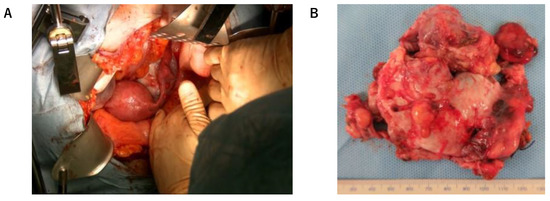

Intraoperatively, the left ovarian tumor was approximately 7 cm in size and adhered to the rectum. Extensive peritoneal dissemination (max. 3 cm) was observed (Figure 2A,B). First, we removed the left ovary. The intraoperative pathological diagnosis of the tumor in the left ovary was malignant struma ovarii (follicular carcinoma). Since the patient elected to not preserve fertility, total hysterectomy, bilateral salpingo-oophorectomy, and omentectomy were performed. After the operation, >2 cm of peritoneal dissemination remained (suboptimal surgery).

Figure 2.

(A) Left ovarian tumor at laparotomy; (B) Resected tumor.